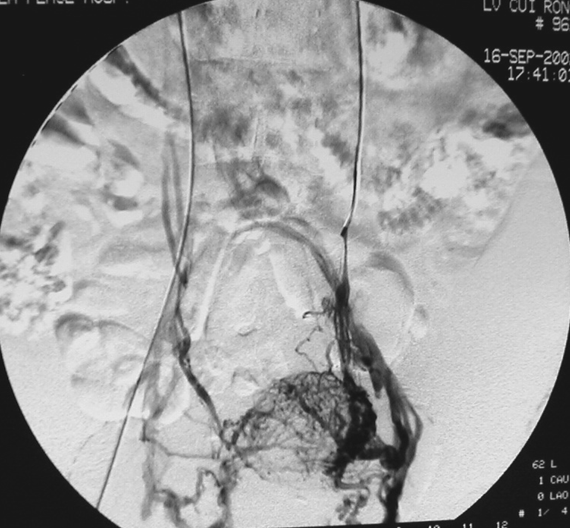

图:双侧卵巢静脉造影

有创金标准:静脉导管造影

地位:诊断PCS的“金标准”,但属于有创操作。

适用情况:通常不用于初步诊断,而是在诊断不明确或已决定同期行介入栓塞治疗时进行。可最直观地显示反流路径、范围及侧支循环。